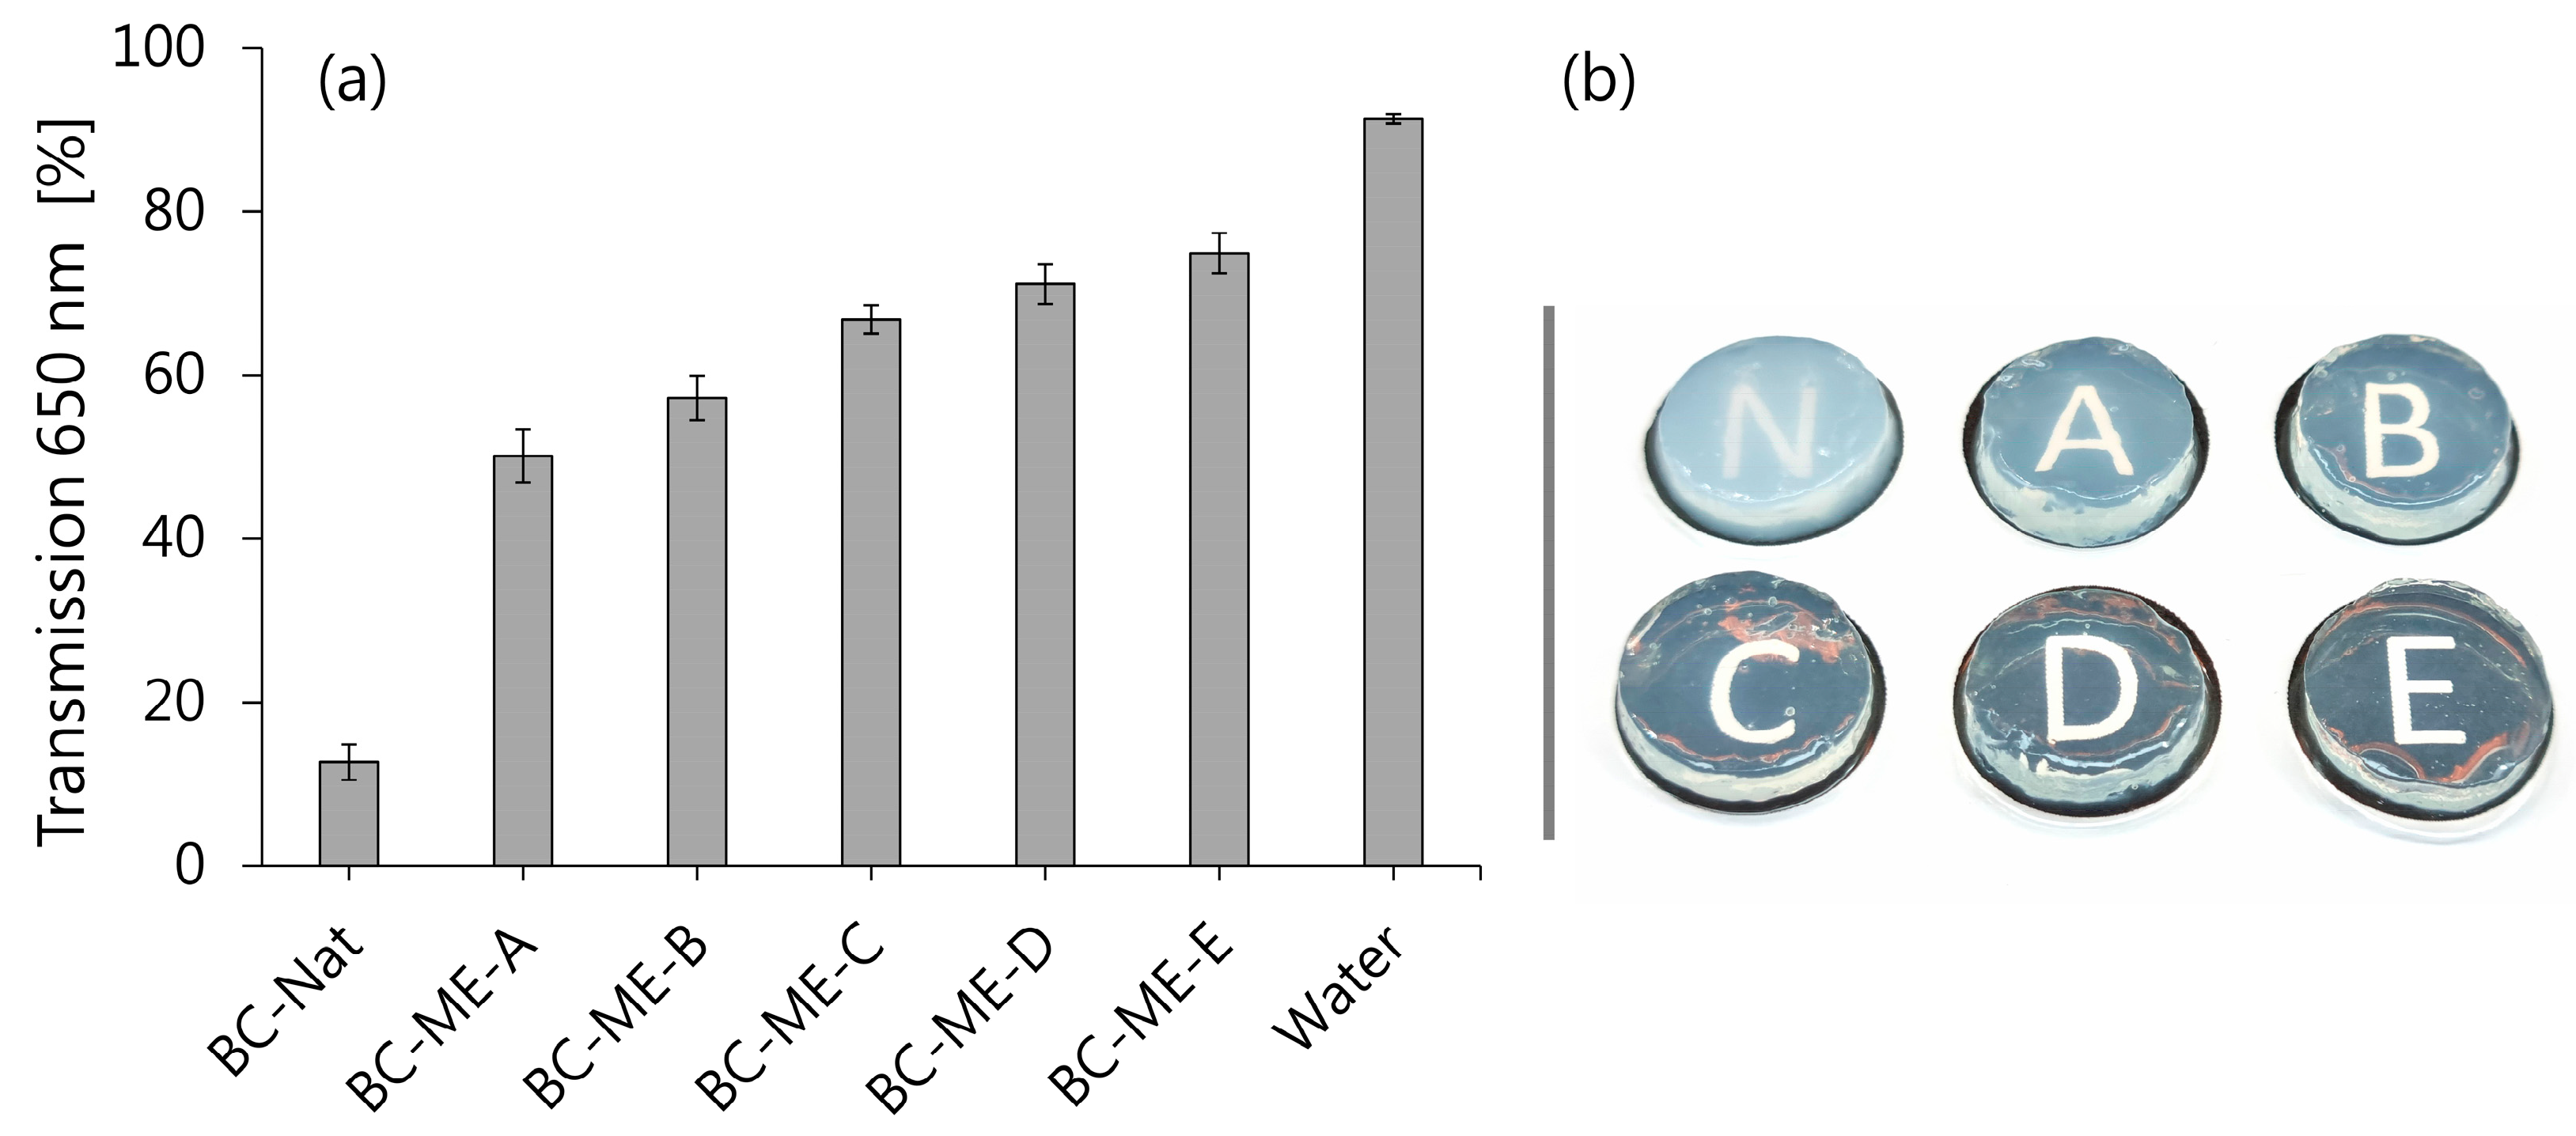

3.3.2. Transparency

3.3.3. FF-TEM of BC-ME